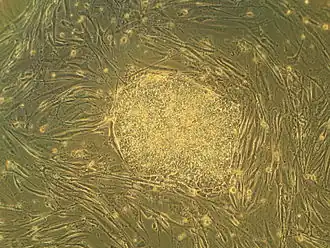

The discovery of stem cells by McCulloch and Till is the basis for all modern stem cell research.

The discovery of insulin at the University of Toronto by Banting and Best in 1921 is considered among the most significant events in the history of medicine.[14][166] The stem cell was discovered at the university in 1963, forming the basis for bone marrow transplantation and all subsequent research on adult and embryonic stem cells.[167] This was the first of many findings at Toronto relating to stem cells, including the identification of pancreatic and retinal stem cells.[168][169] The cancer stem cell was first identified in 1997 by Toronto researchers,[170] who have since found stem cell associations in leukemia, brain tumours and colorectal cancer.[171][172] Medical inventions developed at Toronto include the glycaemic index,[173] the infant cereal Pablum,[174] the use of protective hypothermia in open heart surgery[16] and the first artificial cardiac pacemaker.[16] The first successful single-lung transplant was performed at Toronto in 1981, followed by the first nerve transplant in 1988,[175] and the first double-lung transplant in 1989. Researchers identified the maturation promoting factor that regulates cell division, and discovered the T-cell receptor, which triggers responses of the immune system.[176] The university is credited with isolating the genes that cause Fanconi anemia, cystic fibrosis and early-onset Alzheimer's disease, among numerous other diseases.[177] Between 1914 and 1972, the university operated the Connaught Medical Research Laboratories, now part of the pharmaceutical corporation Sanofi-Aventis. Among the research conducted at the laboratory was the development of gel electrophoresis.[178]